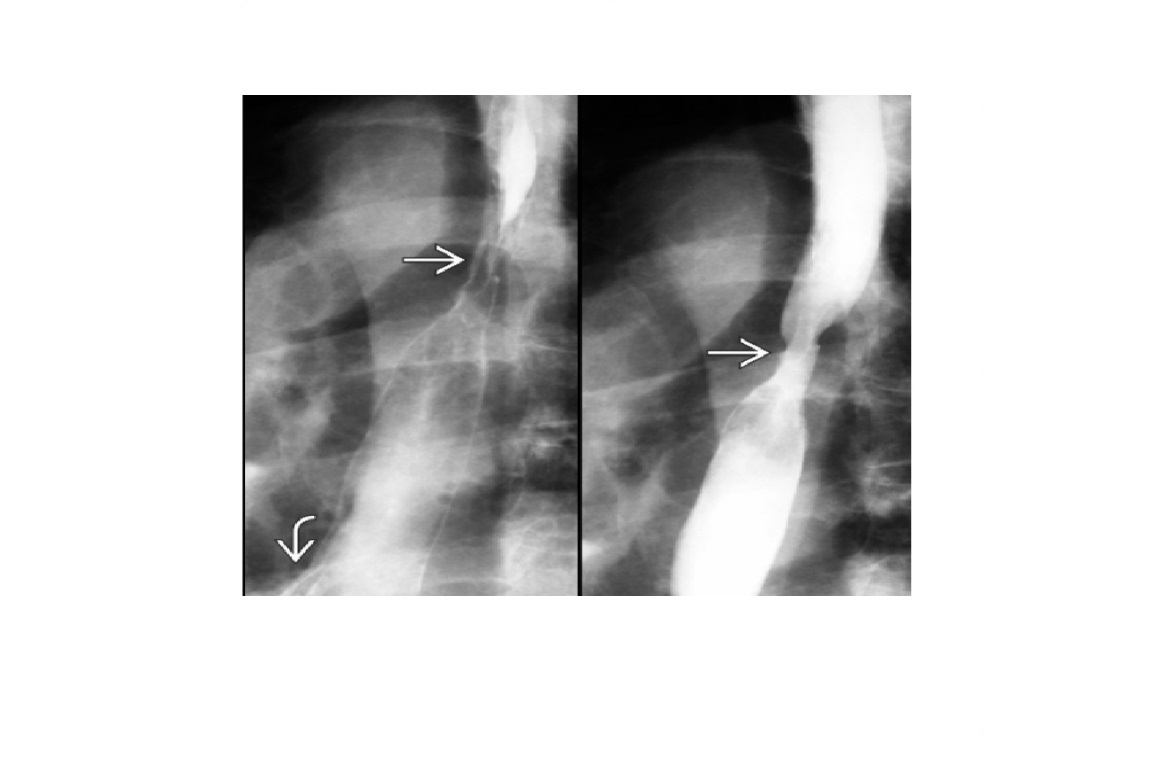

Carcinoid

spiculated mesenteric mass with calcification/ desmoplastic reaction

Tethering of SB loops

90% arise in terminal ileum/appendix

Hyper-vascular liver mets - Carcinoid syndrome

111I- Octreotide scans (1st - highest sensitivity)

or 123I-MIBG (for 10% dont take up octreotide)

for Dx and staging

Big centres use gallium PET

Assocaited with MEN 1 or MEN 2a